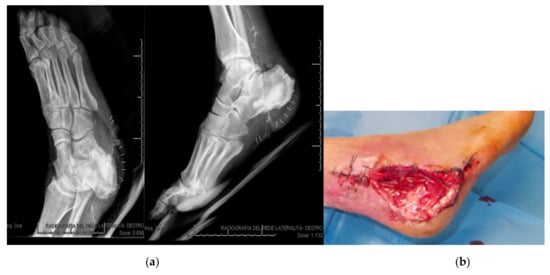

3.3. Lesions Involving Distal Tarsus & Talus